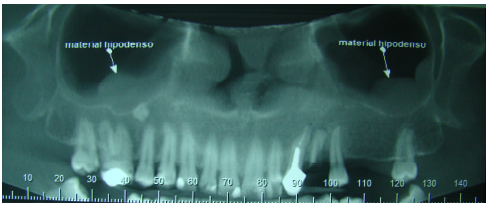

Observando a imagem abaixo e sabendo que não há sintomatologia relatada pelo paciente, marque a alternativa que corresponde ao diagnóstico radiográfico do material hipodenso: